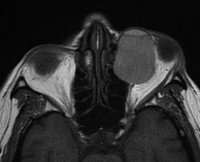

• УЗИ глаза. Ультразвуковое исследование применяется для изучения степени дифференциации органа зрения, состояния заднего сегмента глаза при помутнении оптических сред. При анофтальме в полости орбиты глазное яблоко не определяется или удается выявить его низкодифференцированный зачаток.

• КТ головы. Позволяет диагностировать поражения нервной системы, включающие такие врожденные пороки, как аплазия мозолистого тела, гипоплазия мозжечка, водянка головного мозга, дисплазия коры.